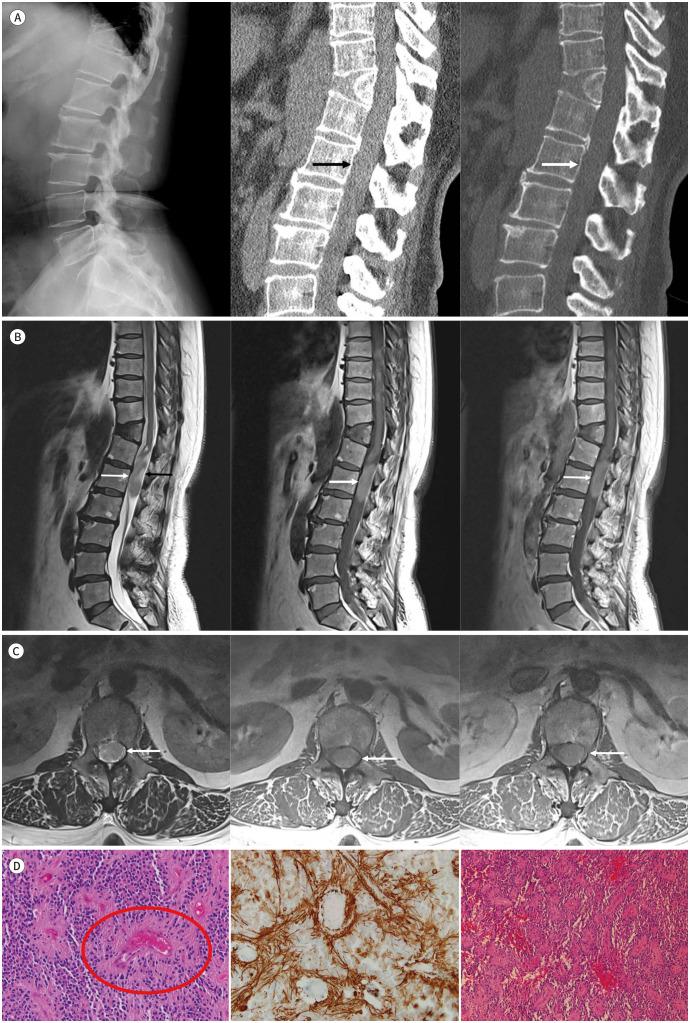

Spinal ependymomas are generally located in the intramedullary compartment in adults. Intradural extramedullary spinal ependymomas are extremely rare. Spinal ependymomas show various contrast enhancements on MRI. In this study, we report a rare case of a 52-year-old female who had a pathologically confirmed intradural extramedullary ependymoma that showed no enhancement on MRI.

脊髓室管膜瘤在成人中通常位于髓内。硬脊膜内髓外脊髓室管膜瘤极为罕见。脊髓室管膜瘤在磁共振成像(MRI)上表现出各种强化。在本研究中,我们报告了一例罕见病例,一名52岁女性,经病理证实为硬脊膜内髓外室管膜瘤,在MRI上无强化表现。